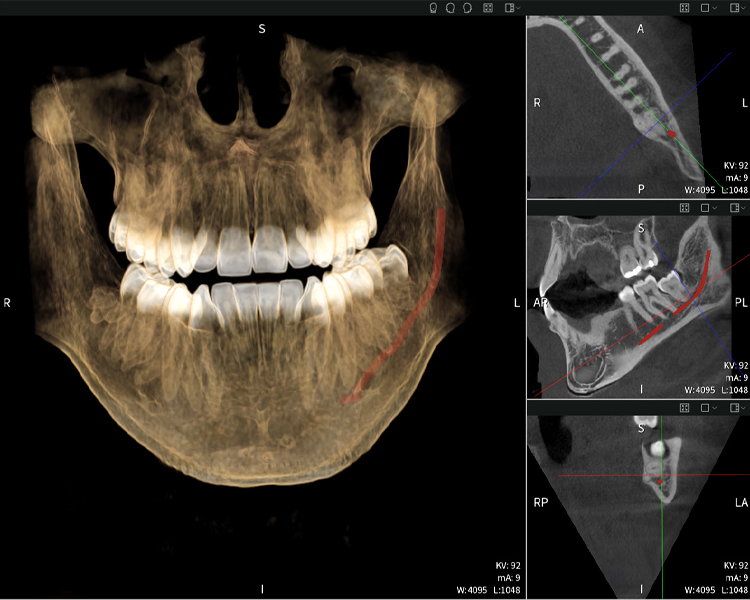

Abbildungen b–d zeigen verschiedene Ansichten einer 3D-Rekonstruktion des Unterkiefers und bieten eine umfassende Übersicht über die Anatomie des Unterkiefers, die Lage der Nerven im Verhältnis zu den Zähnen und ermöglichen die Beurteilung der Zahnsymmetrie und Ausrichtung.

Abbildung d zeigt den bereits vorbehandelten Zahn 48, dessen Krone entfernt wurde und dessen Wurzeln nahe am Nerv belassen wurden, was das hohe Risiko einer Nervenschädigung verdeutlicht.

Abbildung e: Panoramaröntgenaufnahme dient der initialen Beurteilung und zeigt die allgemeine Zahnstellung sowie mögliche pathologische Veränderungen auf. Insbesondere ist auf der rechten Seite (Zahn 48) die Situation nach einer Kronenamputation durch einen externen Behandler ersichtlich. Die beiden stark gekrümmten Wurzeln verbleiben in enger topographischer Beziehung zum Nervus alveolaris inferior im Knochen. Dies deutet auf eine bewusste Entscheidung zur Vermeidung eines erhöhten Risikos einer Nervenläsion während einer vollständigen Extraktion hin und stellt einen klinisch relevanten Befund dar. Zusammenfassend liefern die CBCT-Aufnahmen mit Seethrough Max entscheidende Informationen über die komplexe Anatomie und die kritische Beziehung zwischen den Weisheitszähnen und dem Nervus alveolaris inferior. Diese detaillierte präoperative Diagnostik ist unerlässlich für die sichere und erfolgreiche Durchführung chirurgischer Eingriffe im Unterkieferbereich.